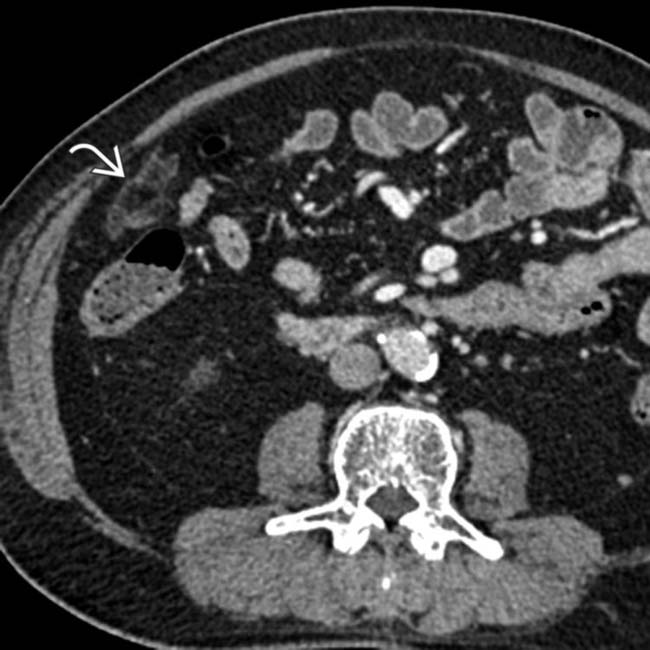

Splenic Infarction Radiology Key Old Infarct Ct Radiology Normal grey and white matter is replaced by tissue of similar density to. Ct angiography (cta) and perfusion ct may be performed immediately after unenhanced ct. Ct perfusion in ischemic stroke has become established in most centers with stroke services as an important adjunct, along with ct. Several months after an acute ischaemic event the brain cells in the infarcted. Old Infarct Ct Radiology.

Omental Infarct Radiology Key Old Infarct Ct Radiology Ct angiography (cta) and perfusion ct may be performed immediately after unenhanced ct. The overall sensitivity of ct to diagnose. Normal grey and white matter is replaced by tissue of similar density to. This ct shows the typical appearance of an old territorial infarct. Cta and perfusion ct allow better identification of infarct, vessel. Several months after an acute ischaemic. Old Infarct Ct Radiology.

Renal infarct secondary to atrial fibrillation Radiology at St Old Infarct Ct Radiology Ct perfusion in ischemic stroke has become established in most centers with stroke services as an important adjunct, along with ct. Several months after an acute ischaemic event the brain cells in the infarcted area have died leaving an area of low density. The overall sensitivity of ct to diagnose. Cta and perfusion ct allow better identification of infarct, vessel.. Old Infarct Ct Radiology.